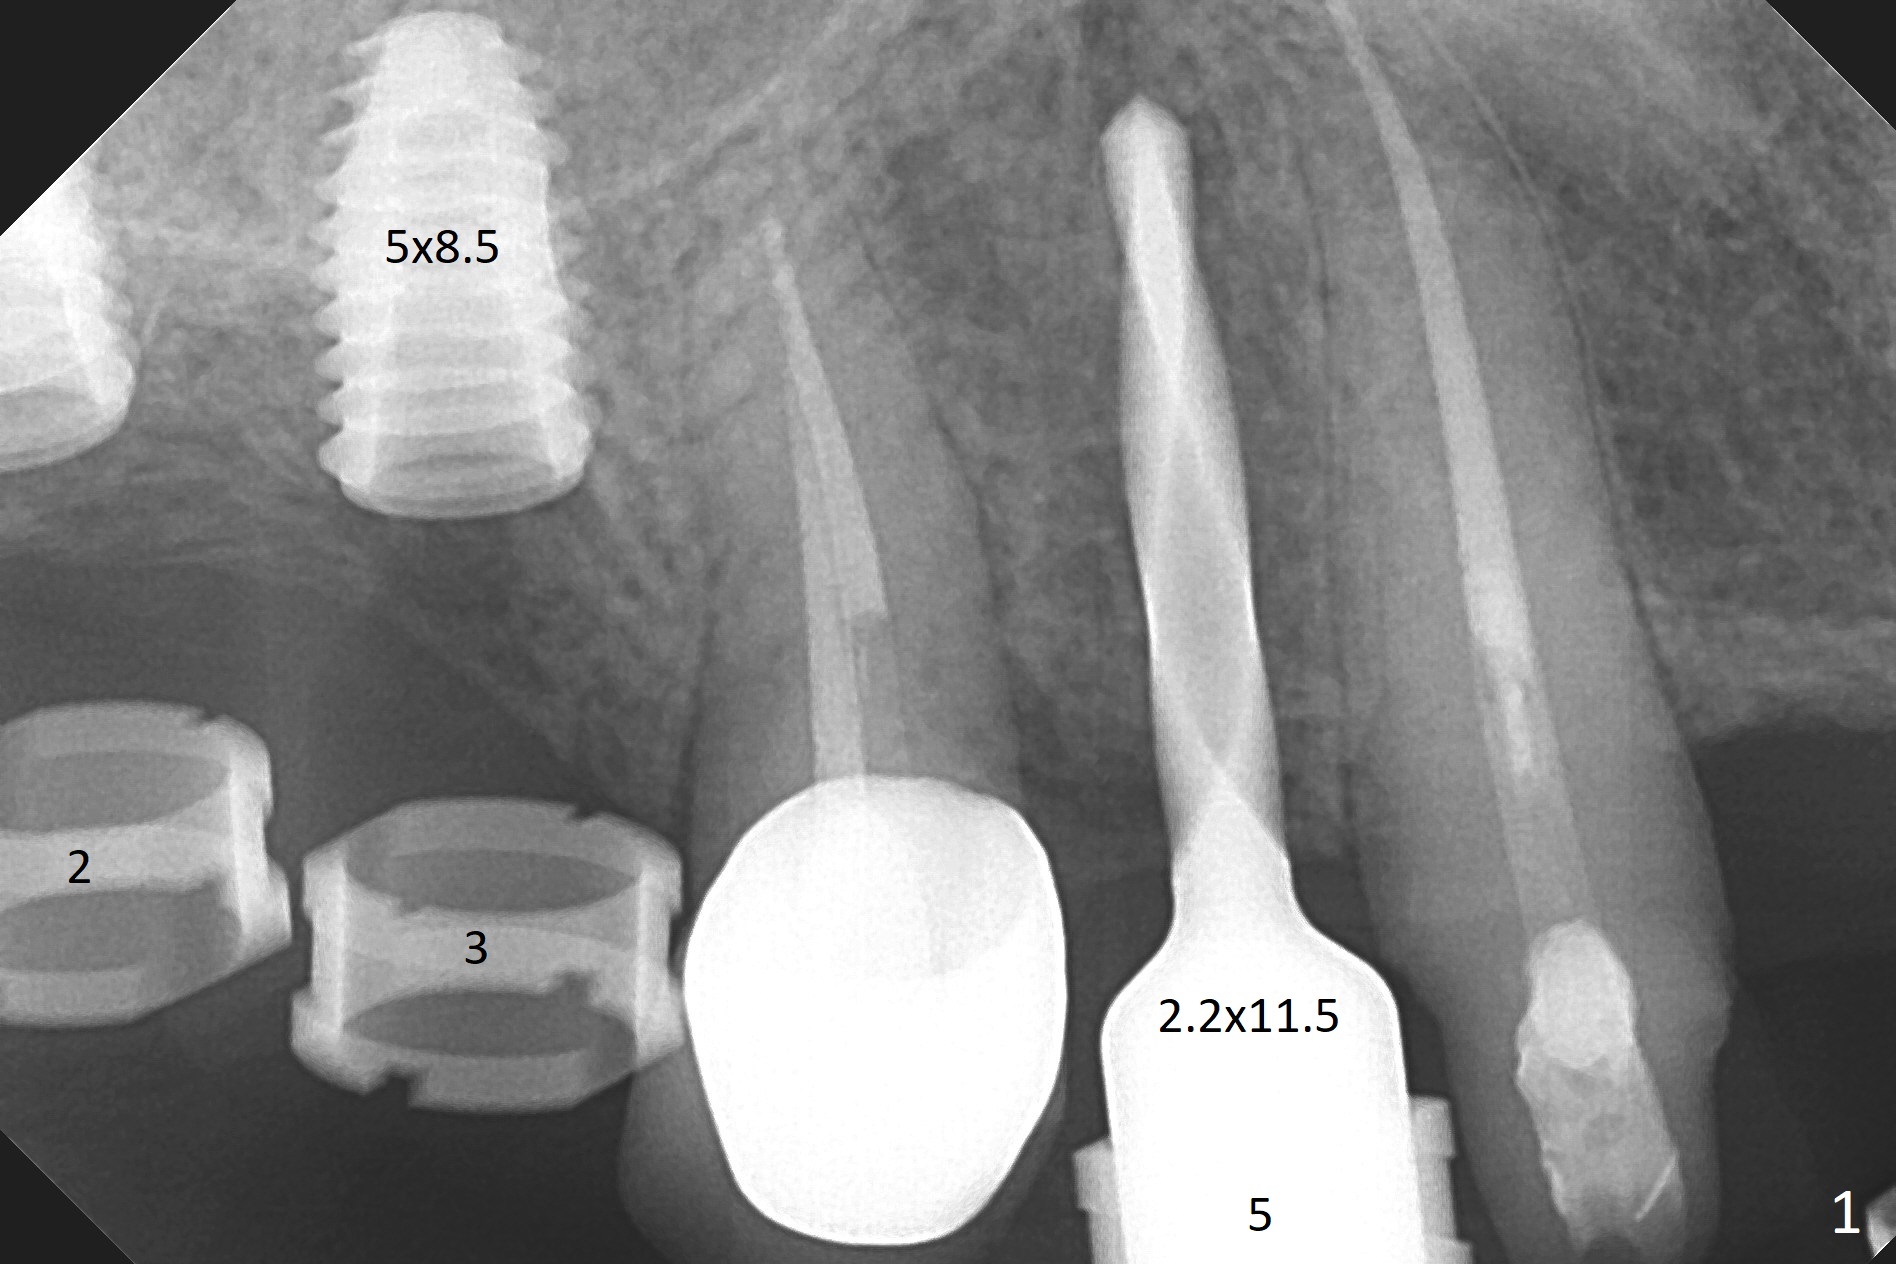

Two of 5x8.5 mm implants are placed at #2 and 3 with sinus lift using water ballooning technique; to avoid invading the neighboring root tips, an intraop PA is taken with a 2.2x11.5 mm drill at #5 (Fig.1). When a 2.5x11.5 mm 1-piece implant is placed at #7, there is 2.4 mm clearance from the impacted tooth (Fig.2). Following 1 mm deeper placement of the 1-piece implant, CT is taken to make sure that the threads are completely covered palatally (Fig.5 P). Interesting is that the sinus membrane is thickened at #2 and 3 (Fig.3 M), as compared to the clear sinus before surgery (Fig.3'). Bone graft is limited in the sinus (Fig.3 arrowheads). The implant at #5 (3.5x11.5 mm) is precisely placed subcrest bucco(B)-palatally (Fig.4). Since the limited field viewed CT does not cover the implant at #2 (Fig.3), immediate postop PA is taken (Fig.6). In fact all of the implants are placed subcrestal, as shown by intraoral X-ray 4 months postop (Fig.7-9). The abutments at #2, 3 and 5 are retorqued (30 Ncm) after crowns' try in and adjustment (Fig.10,11). There is a vertical gap between the implant and abutment at #2 (Fig.11 ^) and a horizontal one at #5 (<). There is apparently no bone loss 1 year 5 months post cementation (Fig.12).